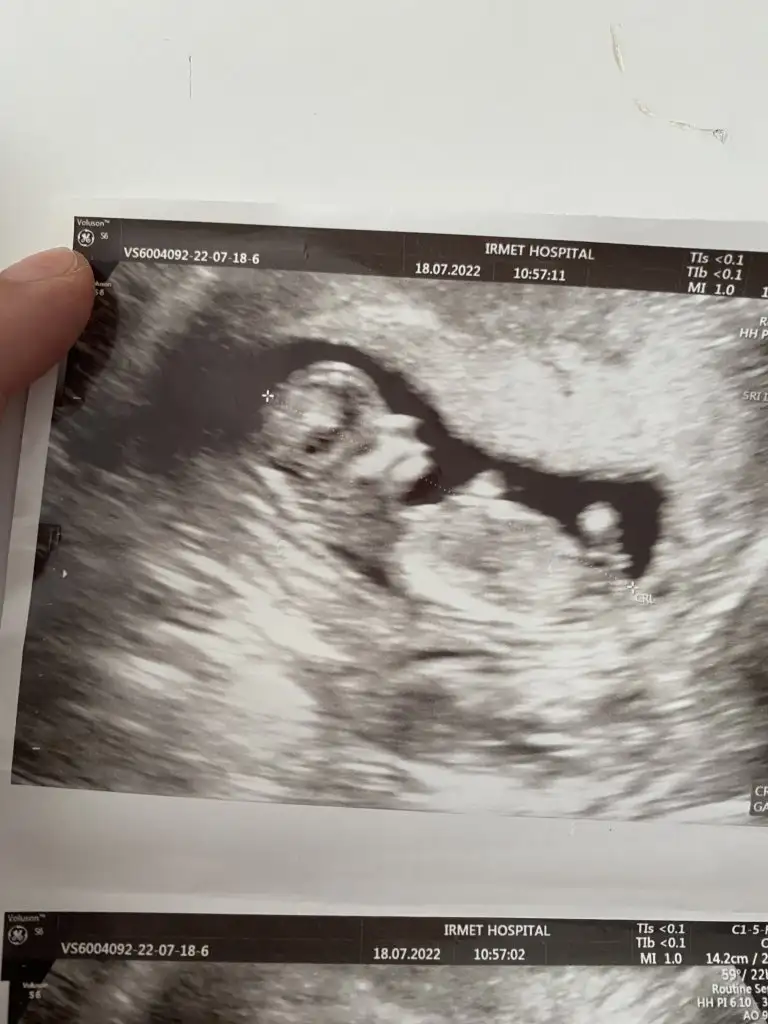

dr soylemeden siz gorun genital nub teorisi ( bebegin cinsiyeti)

Doktor birtürlü emin olamıyor ya nasıl iş anlamadım erkek testisi göremiom dedi kıza benzio ama emin değilim dio kızdır herlde ya

17 haftalık olmuş daha nasıl göremedi anlamadım ilginçmiş valla. Başka bir doktora da gitseydiniz keşke bende perşembe günü gideceğim bakalım bir şey öğrenebilecek miyim